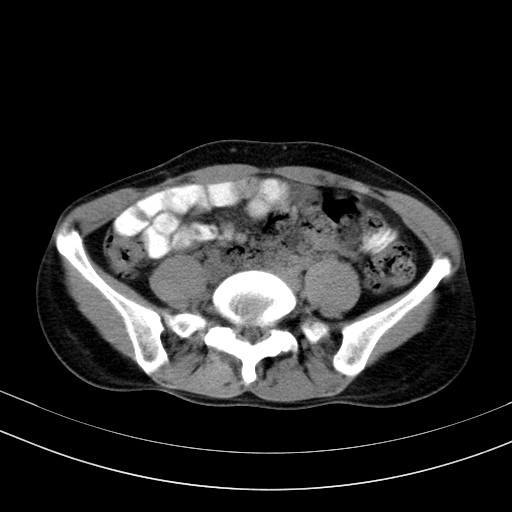

以下是引用卜一在2009-4-7 5:08:00的发言:[br]宫颈癌可能。支持!

以下是引用随光逐影在2009-4-7 8:17:00的发言:[br]考虑宫颈占位性病变(宫颈癌?);建议行进一步检查。

以下是引用jiangjing在2009-4-7 16:46:00的发言:[br]宫颈增大,结构不清,右侧附件区可疑囊样占位,建议增强及mri 检查